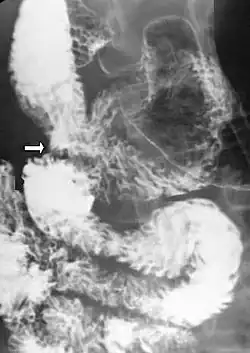

Upper gastrointestinal series showing duodenojejunostomy (white arrow).

If medical treatment fails, or is not feasible due to severe illness, surgical intervention is required. The most common operation for SMA syndrome, duodenojejunostomy, was first proposed in 1907 by Bloodgood.[7] Performed as either an open surgery or laparoscopically, duodenojejunostomy involves the creation of an anastomosis between the duodenum and the jejunum,[23] bypassing the compression caused by the AA and the SMA.[1] Less common surgical treatments for SMA syndrome include Roux-en-Y duodenojejunostomy, gastrojejunostomy, anterior transposition of the third portion of the duodenum, intestinal derotation, division of the ligament of Treitz (Strong's operation), and transposition of the SMA.[24] Both transposition of the SMA and lysis of the duodenal suspensory muscle have the advantage that they do not involve the creation of an intestinal anastomosis.[9]